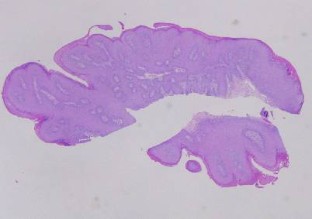

Abb. 2